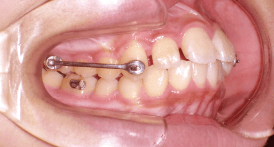

After Motion 3D Appliance 12Weeks - カリエールモーション装着3ヶ月経過 -

カリエールエラスティックを使用し、3か月経過の状態。

第一大臼歯と犬歯の咬合関係にリラップスを想定したオーバーコレクションが見られます。